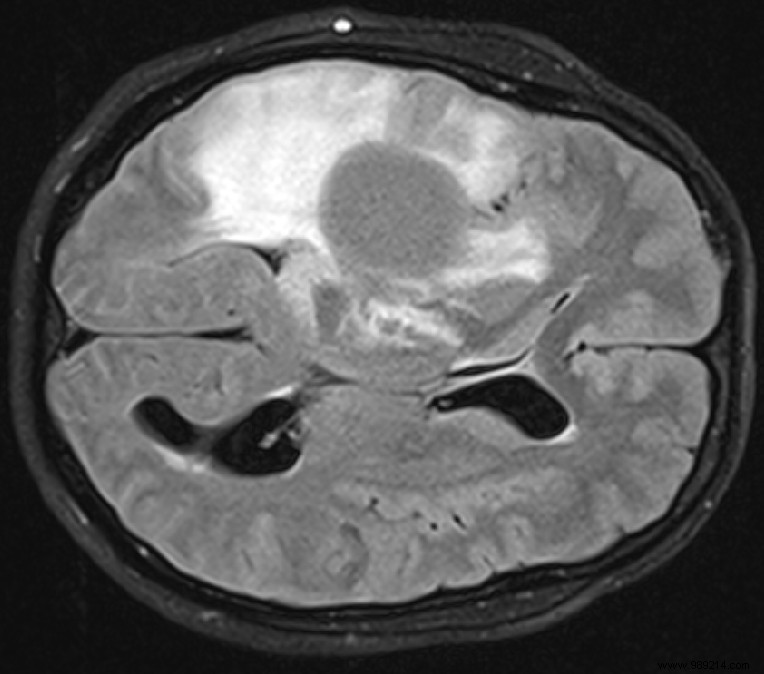

Diffuse low-grade gliomas primarily affect younger patients. These tumors grow slowly at first but often transform into aggressive malignancies within years, posing a serious threat to life expectancy.

Gliomas infiltrate widely across the brain, making complete surgical removal challenging. Chemotherapy and radiotherapy typically offer only modest benefits. For years, researchers at the German Cancer Research Center (DKFZ) have pursued an innovative immunotherapy strategy.